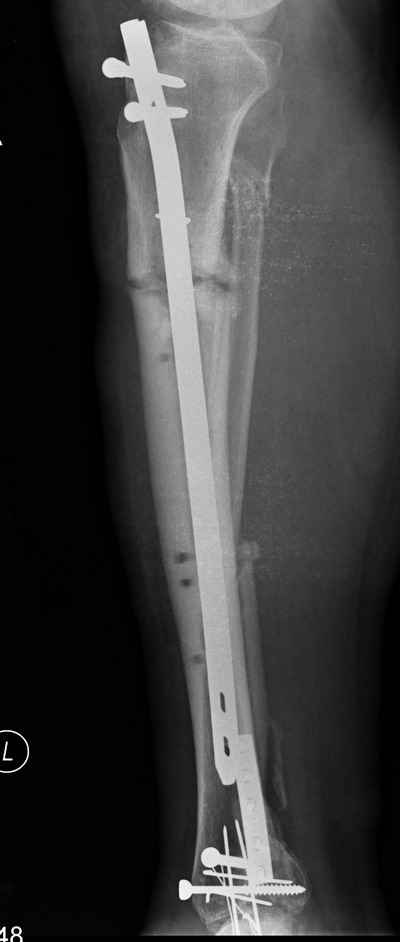

Открытый перелом- пхо+стержневой аппарат-штифтование. Через 4 месяца отек, температура 39….

Удален штифт-резекция+билокальный остеосинтез. Выращивание дистракционного регенерата

Повторное штифтование с рассверливанием. Оставлен дистально «легкий» аппарат для создания компрессии сближенных опилов на 4 недели.